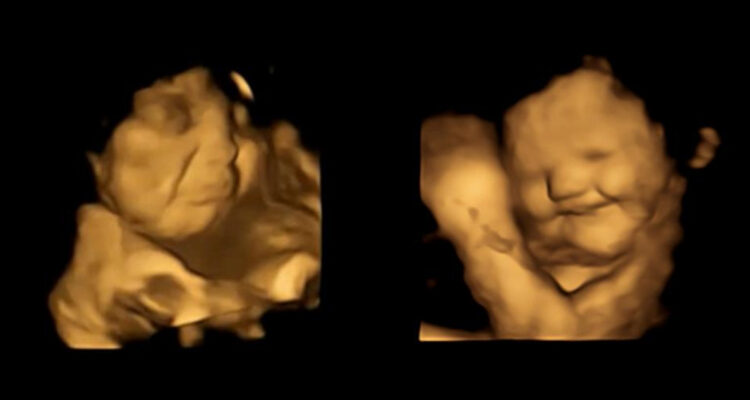

El equipo de especialistas británicos reveló las primeras pruebas que comprueban que los bebés que aún no nacen pueden reaccionar al sabor de los alimentos que consume la madre. Los registros se obtuvieron a través de ecografías en 4D. Las participantes ingirieron zanahorias y kale para que los fetos hicieran diferentes expresiones faciales.

Las imágenes se obtuvieron por medio de ecografías en 4D que se realizaron a más de cien embarazadas. A través de este método, los expertos vieron cómo reaccionaban los fetos a los sabores de algunos alimentos después de que las madres los consumieran.

Los fetos expuestos a la zanahoria mostraron más respuestas de “cara de risa”, mientras que los expuestos al kale (también conocido como col rizada) mostraron más respuestas de “cara de llanto”, explicó la citada universidad en un comunicado.

El equipo, encabezado por Beyza Ustun de la Universidad de Durham, destacó que fue “realmente sorprendente ver la reacción de los bebés no nacidos a los sabores de la col rizada o la zanahoria durante las exploraciones y compartir esos momentos con sus padres”.

El grupo de estudio estaba formado por mujeres de 18 a 40 años, a las 32 y 36 semanas de embarazo, quienes recibieron una cápsula que contenía aproximadamente 400 miligramos de zanahoria o de col rizada en polvo unos 20 minutos antes de cada exploración.

Las reacciones observadas en ambos grupos de sabores, comparadas con las de los fetos de un grupo de control que no se expusieron a ninguno de los sabores, mostraron que la exposición a una pequeña cantidad de sabor a zanahoria o col rizada “era suficiente para estimular una reacción”, indicó la universidad.